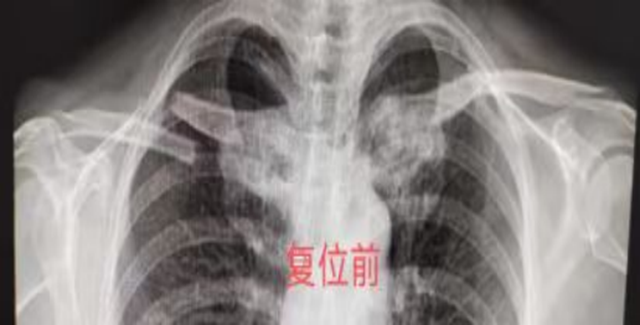

刘孃孃双侧锁骨骨折,断端短缩移位明显,有明确手术指征,但患者本身基础疾病较多,手术治疗风险较大,刘宗超教授综合考虑刘孃孃情况后,决定先行中医正骨复位,保守治疗。

王念武主治医师所在的中医正骨团队仔细阅片后采用中医正骨八法中拔伸牵引、升降提按等手法为刘孃孃进行骨折手法整复,再外敷上本院中医特色院内制剂,用特制的杉树皮小夹板包扎固定。3个月后,骨折愈合,功能也基本恢复。